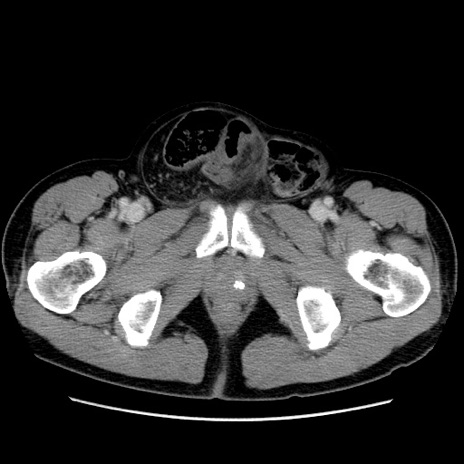

症例34(横断像)

【症例】60歳代 男性

【主訴】右鼠径部膨隆

【現病歴】1年程前より右鼠径部膨隆あり。自己にて還納可能だったため放置していた。3時間前より右鼠径部の脱出を認め、還納困難となり受診。

【既往歴】高血圧

【身体所見】右鼠径部に小児頭大の膨隆あり。弾性硬であり、用手還納は困難。左鼠径部にも膨隆を認める。脱出はなし。

【データ】WBC 15500、CRP 測定なし